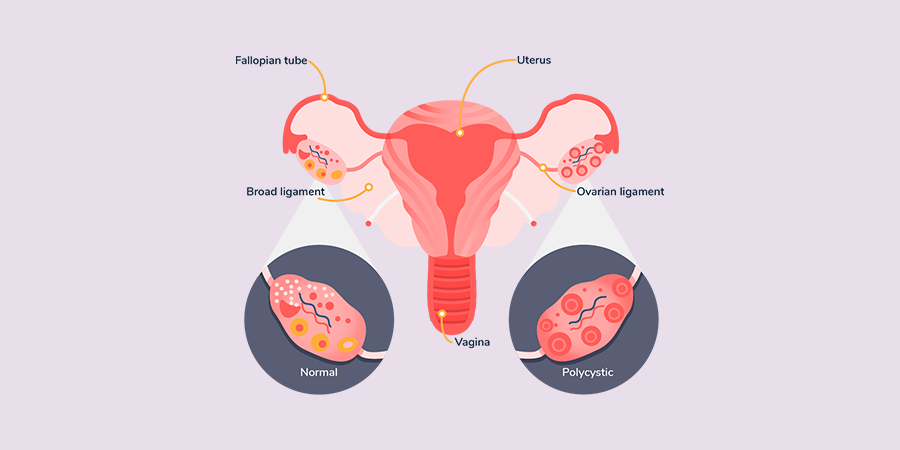

سندرم تخمدان پلیکیستیک (PCOS) نوعی عدم تعادل هورمونی است و زمانی رخ میدهد که تخمدانهای شما (عضوی که تخمک تولید و آزاد میکند) هورمونهای بیش از حد تولید کنند. در افرادی که به سندرم تخمدان پلیکیستیک مبتلا هستند، تخمدانها سطح غیرطبیعی بالایی از هورمونهای مردانه یا آندروژنها تولید میکنند. این امر باعث میشود تعادل هورمونهای تولیدمثل به هم بخورد.

در نتیجه، افرادی که سندرم تخمدان پلیکیستیک دارند، معمولاً چرخههای قاعدگی نامنظم، پریودهای از دست رفته و تخمکگذاری غیرقابل پیشبینی را تجربه میکنند. ممکن است کیستهای کوچک فولیکولی (کیسههای پر از مایع که حاوی تخمکهای نابالغ هستند) بر روی تخمدانها در سونوگرافی مشاهده شود که ناشی از عدم تخمکگذاری (آانوولاسیون) است. با این حال، با وجود نام «پلیکیستیک»، وجود کیست بر روی تخمدانها الزامی نیست و کیستها معمولاً خطرناک یا دردناک نیستند.

کیستها: بسیاری از افراد مبتلا به PCOS تخمدانهایی بزرگتر یا دارای فولیکولهای متعدد (کیسههای تخمک) در سونوگرافی دارند.

تخمدانهای بزرگشده یا ظاهر پلیکیستیک تخمدانها در سونوگرافی: بسیاری از افراد دچار کیست نمیشوند.